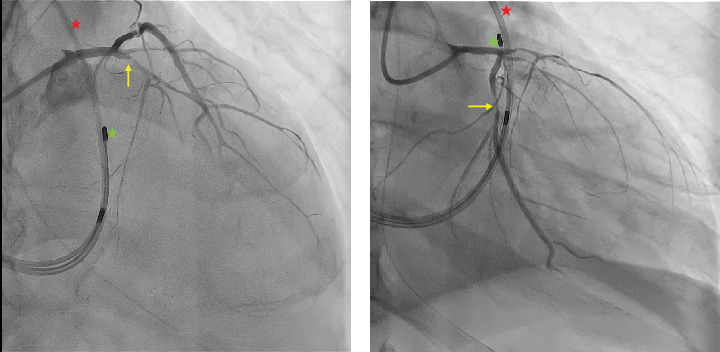

Background: Anterior ST-elevation myocardial infarction (STEMI) is frequently associated with severe complications, such as myocardial dysfunction and conduction abnormalities. Complete atrioventricular block (CAVB), especially when combined with bifascicular block, is a rare but critical presentation that reflects extensive myocardial damage, often linked to proximal left anterior descending (LAD) artery occlusion. Case Presentation: A 76-year-old male with a history of hypertension, diabetes mellitus, and dyslipidemia presented to the emergency department with a 6-day history of gastrointestinal symptoms and recurrent syncope. On arrival, he exhibited bradycardia, hypotension, and mottling, progressing to cardiac arrest. The return of spontaneous circulation was achieved after one cycle of advanced cardiovascular life support. Electrocardiography revealed CAVB with a ventricular escape rhythm displaying right bundle branch block morphology, left anterior fascicular block, and anterior ST-segment elevation. Emergency interventions included endotracheal intubation, Swan-Ganz catheterization, transvenous pacing, and vasopressor support. Echocardiography demonstrated severe left ventricular systolic dysfunction with an ejection fraction of 25%. Coronary angiography identified critical proximal stenoses in the LAD and circumflex arteries, managed with percutaneous coronary intervention and stent placement. Persistent conduction abnormalities and systolic dysfunction necessitated implantation of a cardiac resynchronization therapy defibrillator (CRT-D). Despite extensive rehabilitation efforts, the patient died after 60 days of hospitalization. Discussion: This case highlights the importance of rapid recognition and intervention in anterior STEMI complicated by CAVB and bifascicular block, signaling significant proximal LAD involvement. Advanced therapeutic options, including CRT-D, are crucial for addressing these rare, life-threatening conduction disturbances. The fatal outcome underscores the need for vigilant follow-up and individualized preventive strategies to improve prognosis in such complex STEMI cases.